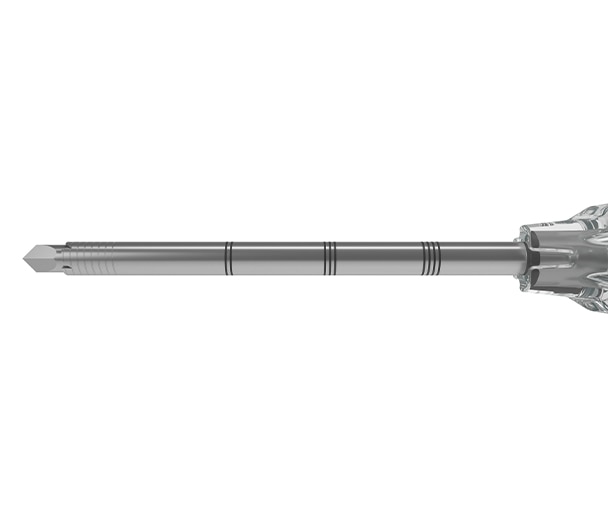

4. Inspect needle components for damaged point, bent shaft or other imperfections prior to use and after each sample is collected. DO NOT USE the device if any imperfection is noted. 5. Applying too much axial force may bend the needle.